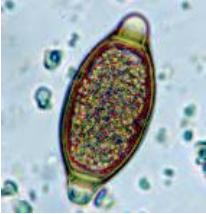

Um levantamento sobre disposição de esgotos domésticos no rio que recorta a cidade detectou na análise parasitológica a seguinte estrutura:

Podemos afirmar, de acordo com a figura, que se trata de um